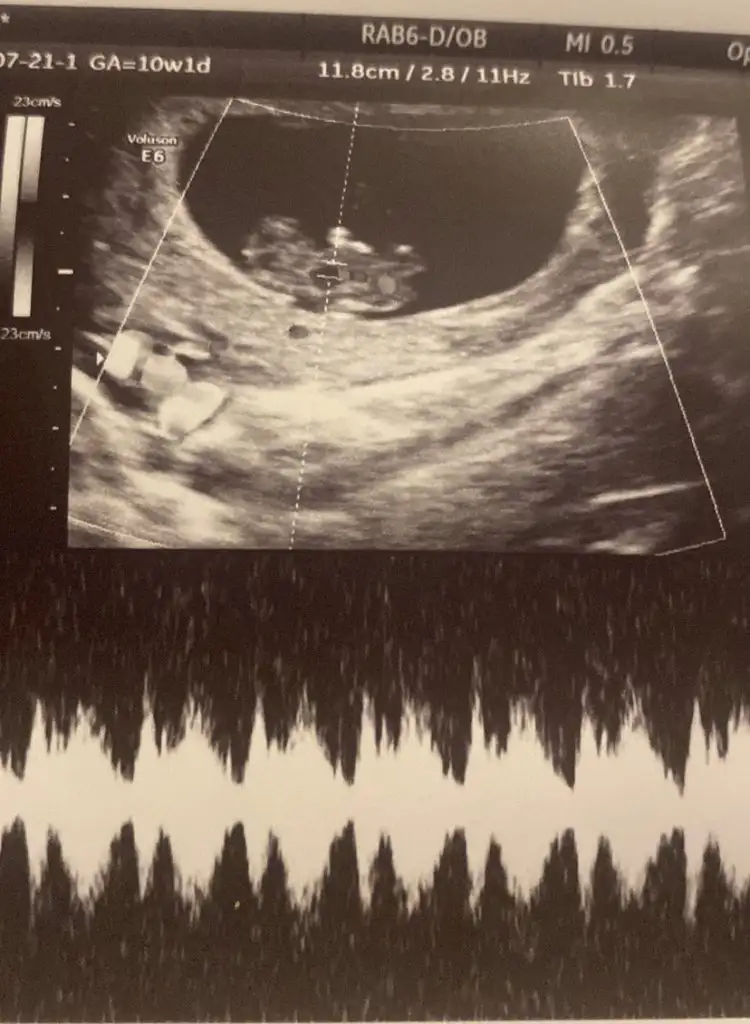

Bir resimde nubu belli ve düz gidiyor oradan kız olduğu anlaşılıyor. Çene sivri geliyor ve bunun içinde kız diyorlar ama sivri çene için çok emin olamasamda eğer pozisyonundan dolayı nubu düz çıkmadıysa bebecik kız. Bir dahaki kontrol ne zaman? Rabbim sağlıkla almayı nasip etsin kucağınıza, öğrenince mutlaka yazın merak ettin şimdiden.Kıza benzettim ben

Kiza benziyor saglikla gelsinEki Görüntüle 3293892 Bizede tahmin yapabilir misiniz 10 haftalığız merak ediyorum çok sevinirim :)

Birazcık küçüğüz sanırım hafta olarak. Kız gibi ama ilerleyen haftalarda tekrar baksak iyi olur.Bize de tahminde bulunur musunuz